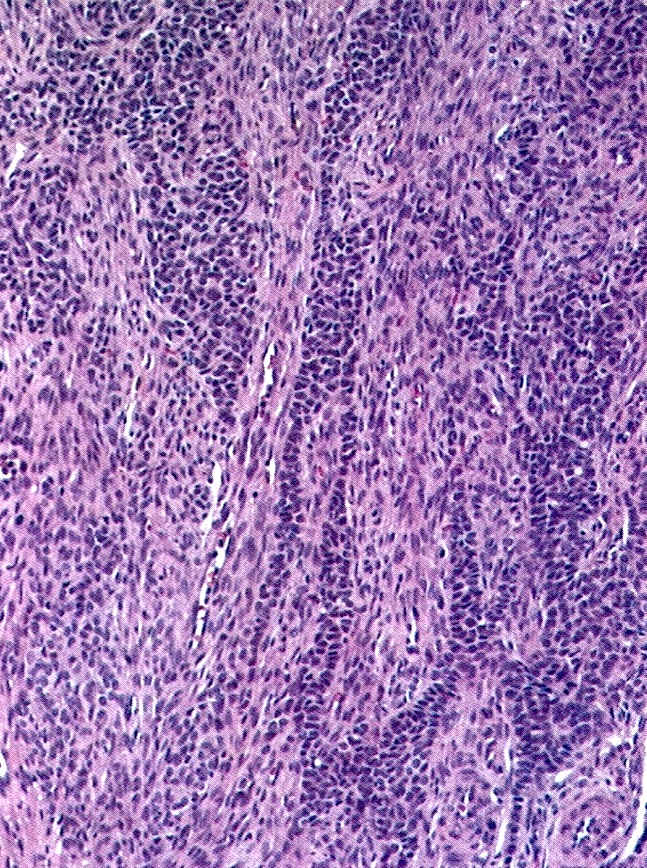

Microscopic (histologic) description

- Small, bland, cuboidal to polygonal cells with scant cytoplasm and pale, uniform angulated and usually grooved nuclei (coffee bean)

- Various patterns, including diffuse (the most common), trabecular and corded, insular, microfollicular (resembling Call-Exner bodies of the Graafian follicles: small follicle-like structures filled with eosinophilic material) and macrofollicular (the least common)

- Usually a mixed growth pattern is seen

- Mitotic activity is usually not brisk (< 3/10 high power fields)

- Stroma is usually hypervascular with variable amounts of fibroblasts and theca cells

Microscopic (histologic) images

Contributed by Shabnam Zarei, M.D. and Sharon Bihlmeyer, M.D.

AFIP images